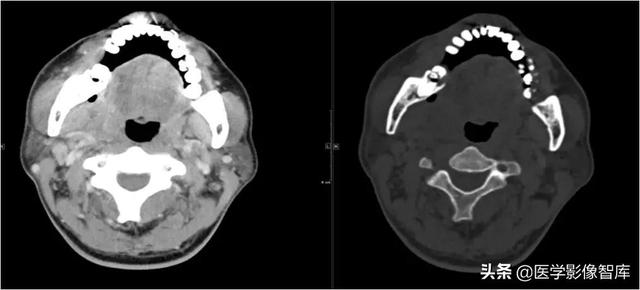

咀嚼肌间隙、颌下间隙、左侧颞下间隙,颊间隙,翼颌间隙

男,55岁,左下后牙反复肿疼1年余,加重1月余,疼痛剧烈伴张口受限,面部肿胀。

咀嚼肌间隙有脓肿形成。